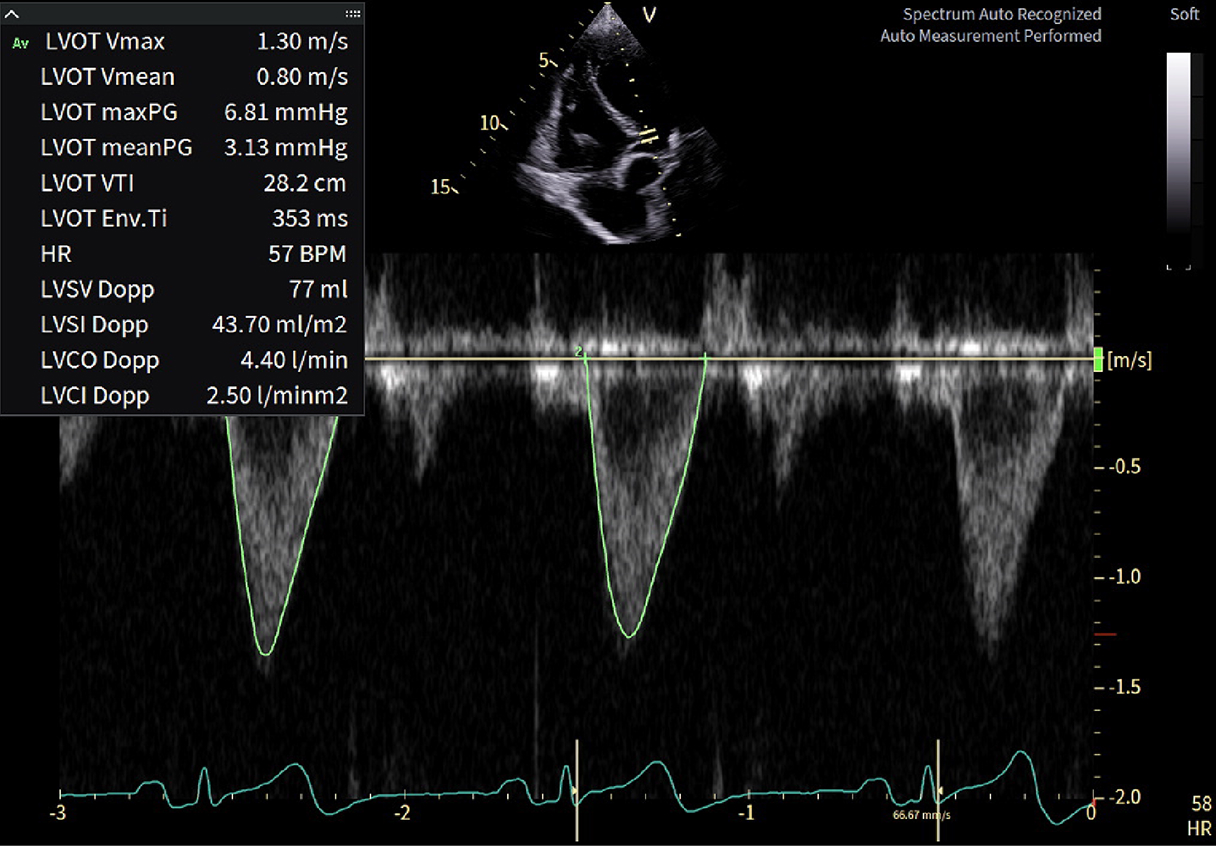

Caso condiviso da Marcello De Santis